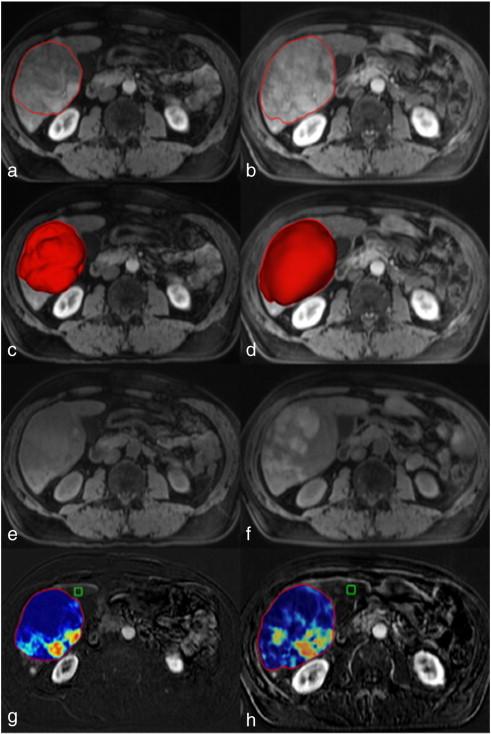

Fifteen patients with 59 lesions who underwent MR imaging before and 3 to 4 weeks after the first TACE were retrospectively included. MR analysis evaluated signal intensities, World Health Organization (WHO), Response Evaluation Criteria in Solid Tumors (RECIST), European Association for the Study of the Liver (EASL), modified RECIST (mRECIST), tumor volume [volumetric RECIST (vRECIST)], and volumetric tumor enhancement [quantitative EASL (qEASL)]. qEASL was expressed in cubic centimeters [qEASL (cm(3))] and as a percentage of the tumor volume [qEASL (%)]. Paired t test with its exact permutation distribution was used to compare measurements before and after TACE. The Kaplan-Meier method with the log-rank test was used to calculate overall survival for responders and non-responders.

In target lesions, mean qEASL (%) decreased from 63.9% to 42.6% (P = .016). No significant changes were observed using the other response criteria. In non-target lesions, mean WHO, RECIST, EASL, mRECIST, vRECIST, and qEASL (cm(3)) were significantly increased compared to baseline. qEASL (%) remained stable (P = .214). Median overall survival was 5.6 months. qEASL (cm(3)) was the only parameter that could predict survival based on target lesions (3.6 vs 40.5 months, P < .001) or overall (target and non-target lesions) response (4.4 vs 40.9 months, P = .001).